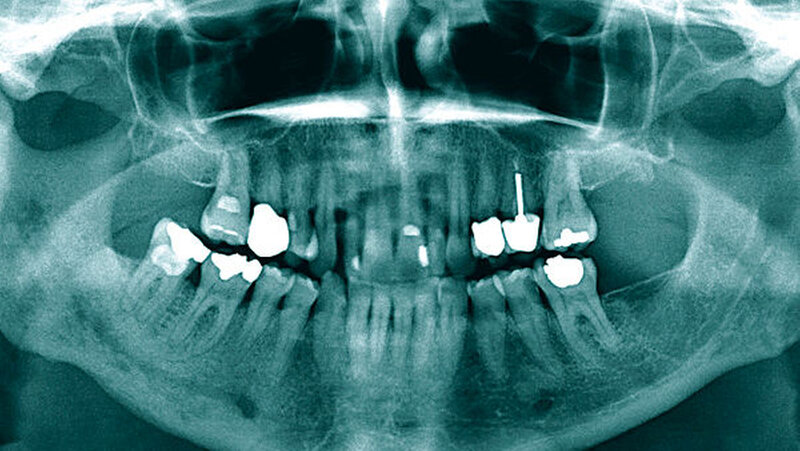

Den Pathomechanismus erklären die Autoren so: „Zuvor bestrahltes Kopf- und Halsgewebe wird hypovaskulär und hypoxisch. Befindet sich der Unterkiefer im Bestrahlungsfeld, kann er eine aseptische, avaskuläre Nekrose entwickeln, die zu Infektionen, Zahnverlust und sogar zu pathologischen Kieferbrüchen führen kann.“ [Davis et al., 2022]. Klinisch zeigt sich intraoral zumeist freiliegender Kieferknochen. Gleichzeitig können Schmerzen sowie Fistelungen, erhöhte Zahnbeweglichkeit und Sequestrierungen auftreten.

Bei Verdacht auf eine ORN sollten diagnostische Maßnahmen eingeleitet werden. Dazu zählt, neben einer Bildgebung, auch die histologische Überprüfung. Die Therapie sollte ebenfalls durch einen Facharzt erfolgen.